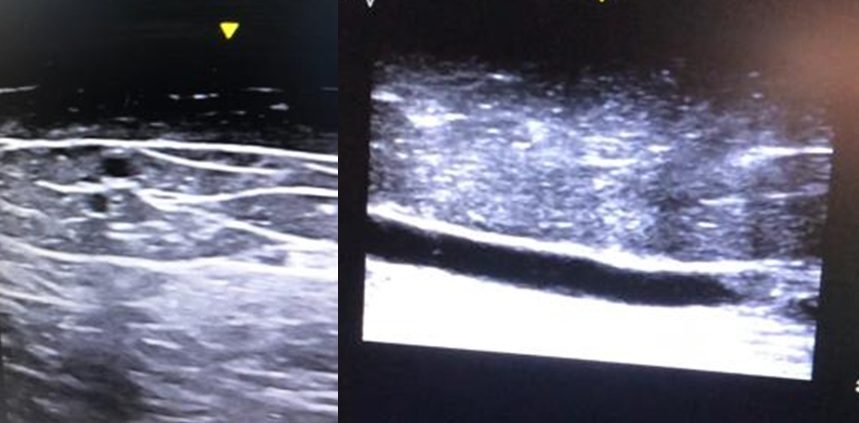

قبل بدء الاجراء ، سيتم استعمال جهاز الصوناربواسطه الجراح لتحديد الأوردة الاساسيه التي تحتاج إلى علاج

من خلال المدخل يتم ادخال قسطرة الليزر داخل ا في الوريد تحت توجيه الصونار. تمر قسطره الليزر بطول الوريد الصافي بالكامل.

. يتم إعطاء الحقن المخدر على طول خط الوريد تحت توجيه الصونار